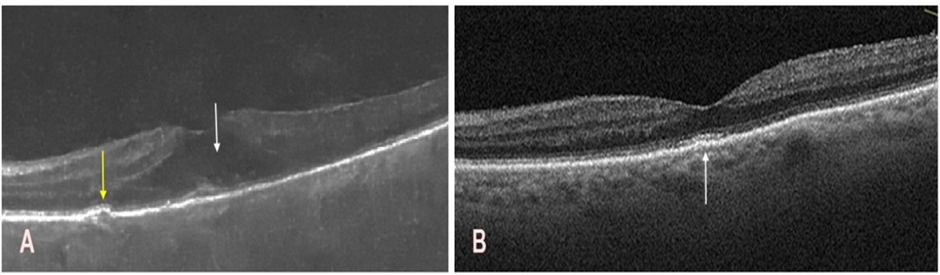

In parallel, treatment for exudative AMD was initiated in the right eye. This included four intravitreal injections of the anti-VEGF agent faricimab (Vabysmo, Roche Pharma AG, Grenzach-Wyhlen, Germany) at monthly intervals before cataract surgery, resulting in a favorable therapeutic outcome. Lesion regression was confirmed using macular OCT (Figure 4A,B).

Figure 4: Optical coherence tomography of the macula in the right eye before and after intravitreal faricimab injections. A. Before injections, a hyperreflective subretinal, subfoveal structure was noted (white arrow), accompanied by a hyporeflective subretinal space (yellow arrow). These findings are indicative of active macular neovascularization. B. After four injections, restoration of the foveal contour is visible, with mild irregularities of the retinal pigment epithelium and photoreceptor layers (white arrows).

Following improvement in the transparency of the optical media, left macular OCT revealed exudative age-related macular degeneration (Figure 6A), which was treated as in the right eye, resulting in improved retinal morphology and suppression of neovascular activity (Figure 6B).

Figure 6: Optical coherence tomography of the macula in the left eye before and after the intravitreal faricimab injections. A. Persistent corneal edema limited fundus visualization and resulted in suboptimal image quality. A hyporeflective space is observed within the intraretinal layers (white arrow), along with a small drusenoid elevation and minor irregularities at the level of the photoreceptors and the retinal pigment epithelium (yellow arrow). B. Restoration of the foveal contour with mild irregularities in the retinal pigment epithelium and photoreceptor layers, predominantly in the subfoveal region (white arrow).